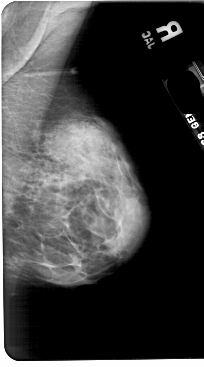

A_1797_1.LEFT_MLO

LEFT_MLO LINES 5491 PIXELS_PER_LINE 3361 BITS_PER_PIXEL 12 RESOLUTION 43.5 OVERLAY